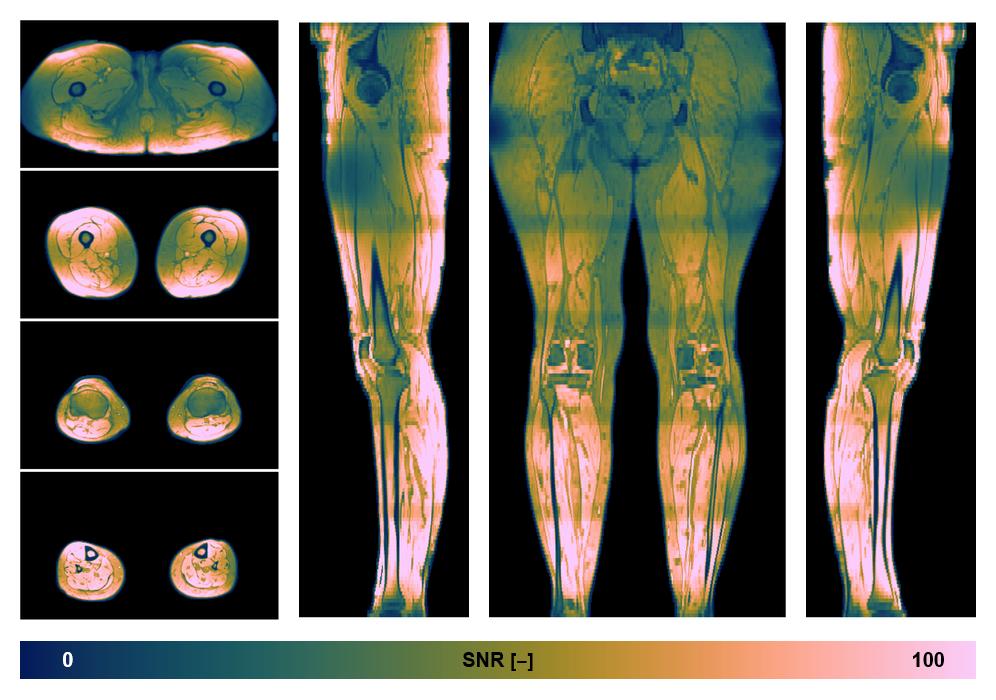

• SNR distribution

The SNR distribution of the dixon data.